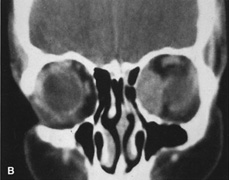

Lateral orbitotomy provides excellent access to deep lesions in the subperiosteal, peripheral, or intraconal space lateral to the optic nerve (Fig. 8A, B).

Fig. 8. Coronal (A) and axial (B) views in an illustration of areas (shaded) amenable to lateral orbitotomy.

Although intraconal lesions medial to the nerve sometimes can be approached laterally, great care to identify and protect the optic nerve is required during deep orbital dissection. Because the eyelid crease incision allows such wide exposure of the superolateral orbit, it is often possible to remove fairly large orbital lesions without removing the lateral orbital wall (Fig. 9). Surgery in this case proceeds as described to exposure of the superior and lateral bony orbital rims. It is not necessary to reflect periosteum over the external surface of the rim. Instead, once periosteum at the rim is exposed, it is cut with cautery and then only the mesial periorbita need be elevated internally to expose orbital contents with subsequent intra-orbital dissection carried out with the lateral rim in place. Often it is preferable to initially attempt to remove intraconal or lacrimal fossa lesions in this fashion. If exposure proves inadequate, the periosteum over the external surface of the lateral orbital rim can be elevated and osteotomies and removal of the lateral wall still can be carried out.